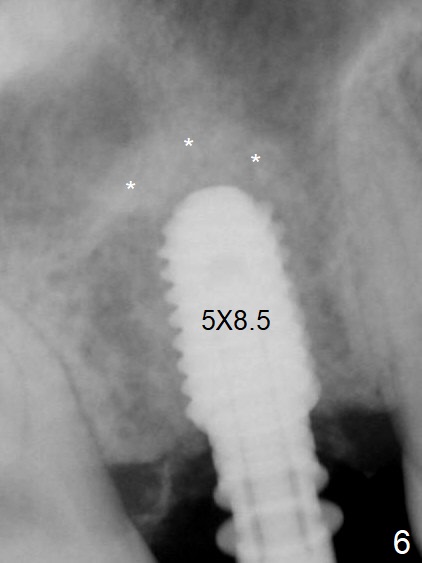

A 54-year-old man has lost the tooth #3 for 6 months with complicated sinus floor morphology (Fig.1 red dashed line (one of 2 outlines), bone height ~ 7 mm). Initial osteotomy depth is ~ 6 mm (Fig.2,3 with 1.2 mm initial drill and DIO Bone Expander 1 (E1 with diameter 1.0/1.6 mm). Following change in the trajectory, E2 (1.3/2.3 mm) is used for ~ 8 mm (Fig.4). After application of E4 (2.4/3.7 mm, Fig.5) and E5 (3.0/4.4 mm) for ~ 12 mm, the sinus membrane is found to have perforated. With placement of collagen membrane and cortical allograft (Fig.6 *), a 5x8.5 mm Hiossen implant is placed with >50 Ncm.